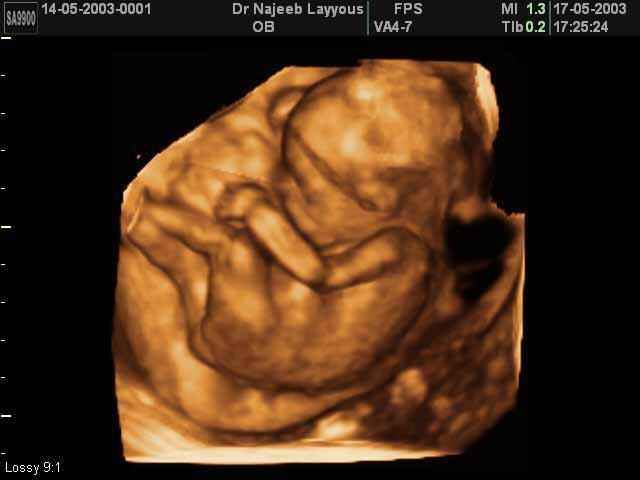

- Fetal Behavior Ultrasound Photos

Ultrasound Photos in 3D showing Fetal Behavior Inside the uterus | Dr N Layyous